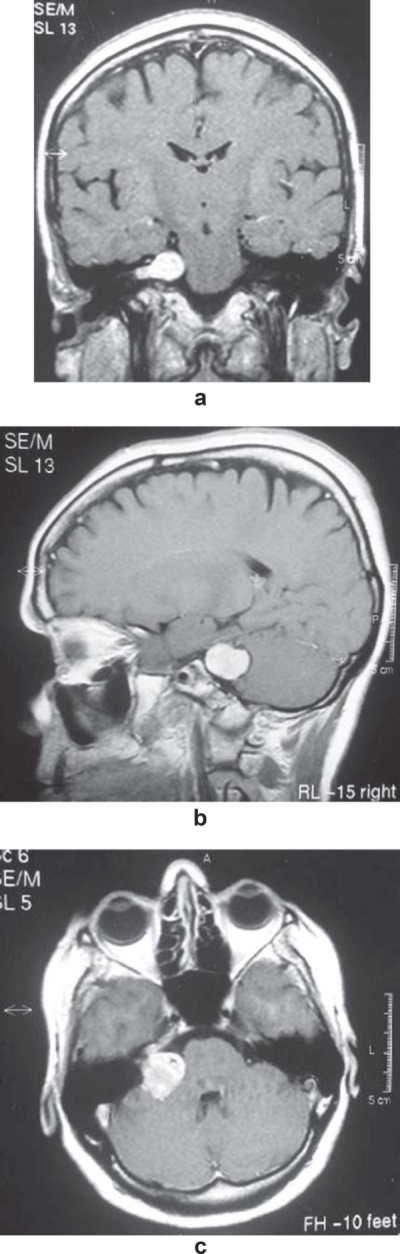

在这个不同的病例中,有迹象和症状表明五支(三叉神经节)疼痛,可能与脑瘤有关。在监督该病例的牙医的建议下,一名医生要求进行核磁共振检查,并在临床检查40天后进行了检查。MRI示右侧椎间盘轻微移位,右侧下降,右侧声通道广泛肿瘤病变,延伸至桥小脑角(图1a),提示前庭神经鞘瘤。

较初,建议的治疗方法是使用消炎药、肌肉松弛药和湿热来减轻局部肌肉疼痛,持续4天。同时,为了稳定咬合,排除牙齿对中枢疼痛的影响,减少异常肌肉活动,降低肌肉疼痛敏感性,制造了密歇根型咬合机。在随访期间,夹板进行了调整,从那一刻起,患者开始在夜间和白天使用夹板,取出夹板只是为了吃东西和清洁牙齿。通过连续的调整和频繁的控制,患者对夹板的使用达到了良好的反应,好转了疼痛的前景。夹板是由于肌肉和骨骼疼痛的存在,提示TMD与稳定剂联合使用。不仅肌肉和骨骼疼痛,包括较大张口,而且神经痛也有好转。病人被咨询给精神科医生,对她的心理状况进行更多方位的评估,结果显示出焦虑和抑郁的症状。病人还被建议去看脑外科医生以评估肿瘤病变(图1b和1c),并调查头晕、眩晕和神经痛。经过医学评估,患者开始服用舍曲林、卡马西平和氯硝西泮,随后疼痛危机减轻。肿瘤被手术切除了。在这个不同的病例中,面神经受损,导致受累侧听力下降和贝尔麻痹。然而,疼痛减轻了,不再影响病人。